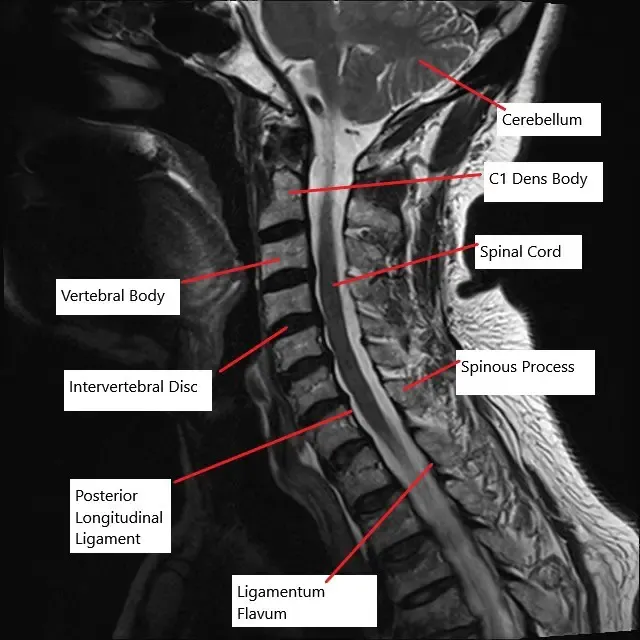

Resonancia magnética de la columna cervical en la sección sagital muestra múltiples discos intervertebrales abultados.

La columna cervical consta de siete vértebras separadas por discos intervertebrales. Estos discos actúan como amortiguadores, permitiendo el movimiento y protegiendo la médula espinal, que atraviesa el canal espinal formado por las vértebras. La médula espinal emite nervios en cada nivel vertebral, que controlan diversas funciones corporales. Cuando las vértebras o discos degeneran, el canal espinal puede estrecharse, comprimiendo la médula espinal o los nervios y provocando diversos síntomas neurológicos.